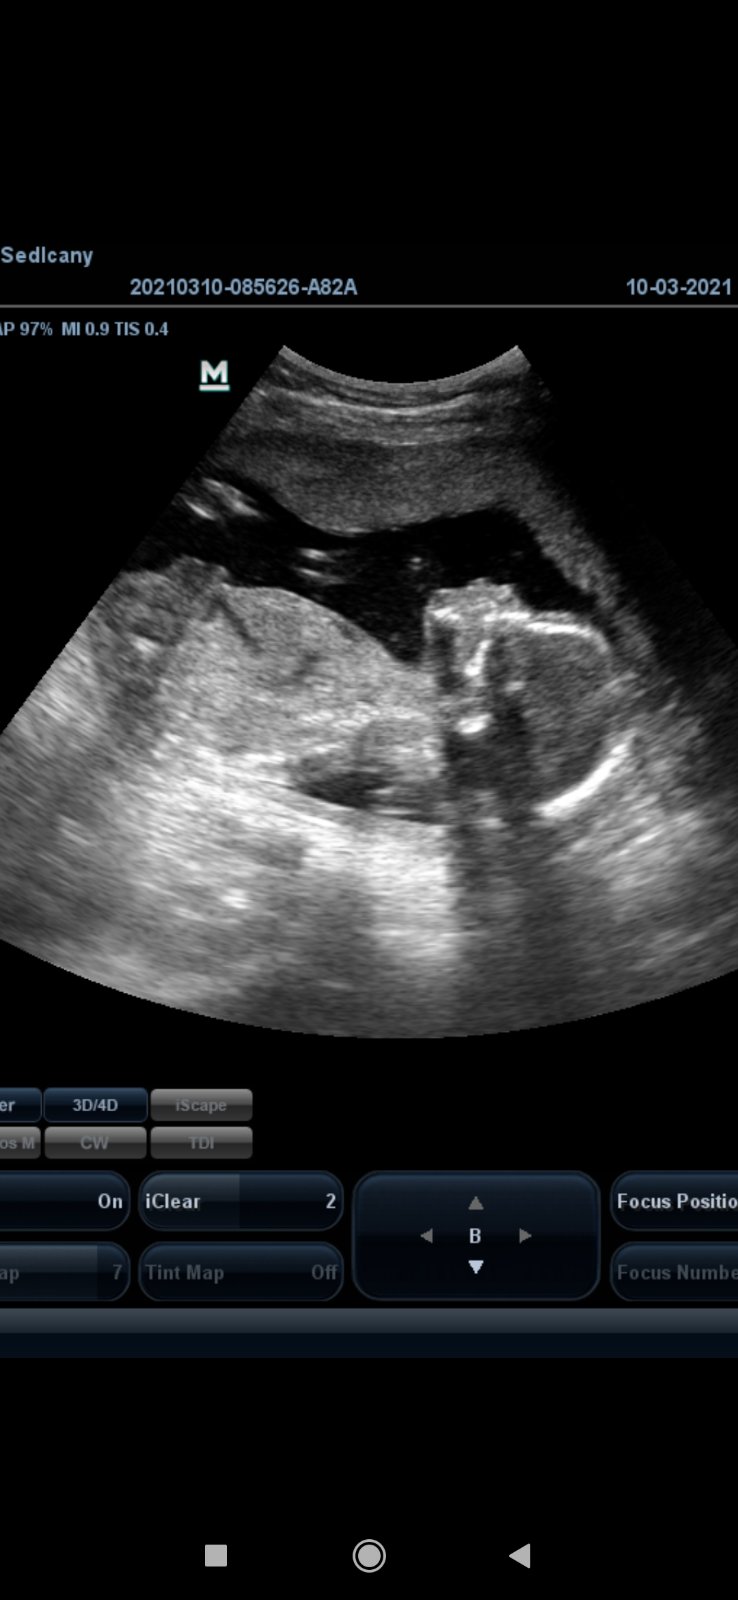

@nagojka je to opravdu co?Jinak jsme zdraví jak já tak prďolka.A čekáme holčičku

@nagojka no tak to třeba já fakt nepoznám ale většinou se na screeningu neseknou 😉😊

@pepickovapavlinka pan doktor rikal ze je to jednoznacne ale muj chlap tomu nemuze nak uverit...dyt ten pindik na te fotce mi prijde celkem jasnej..a on mi tvrdi ze je to prej odraz nohy😂😂😂a stin...priste ho musim za vlasy dotahnout semnou na utz aby to slyset u od profesionala..pohlavi mi dr rekl az ve 20tt...no...a zitra zaciname 23tt...opravdu to neskutecne leti...

Ahoj holky...tak co je u Vas noveho?doufam ze jste vsechny i s mimcama v poradku a vzorne roste..ja byla ve ctvrtek na cukrovce a dnes na kontrole...Cukr v naproste norme-ukazkove...Kluka mame potvrzeneho definitvne..Dle dr odpovida 25+0tt,aplikace hlasi 24+5tt..no a malej ma odhad 792g..uz mi dava pekne zabrat 😂😂🙂🤰🤰